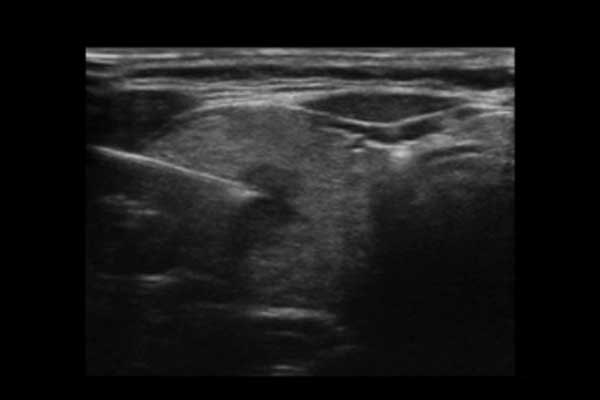

X3便携式彩色多普勒超声诊断系统是一款将小巧机身与卓越性能结合的便携产品。高度集成化的硬件模块,配合时尚前沿的人机工学设计打造了X3,如笔记本电脑般轻薄灵巧的机身、同时也赋予它突破体量限制的优异整机性能。轻便小巧,简单易用。图像清晰,X3可以随时随地满足您的使用需求。

X3搭载了丰富的探头群,可全面满足腹部、泌尿系统、浅表器官、妇科、产科、心脏及外周血管等常规领域应用。轻薄灵巧的主机机身、人性化的台车设计、实用的三探头扩展器、使得它无论在超声科还是在移动诊疗应用中都可以轻松应对。